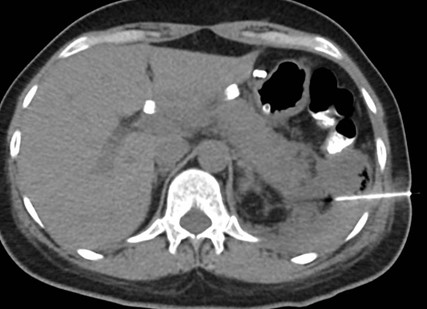

Caso 2

Paciente femenina de 48 años de edad que ingresa a Hospital Sanatorio Franchin por síntomas de cefalea y mareos, cuadro que se hace progresivo, presentando síncopes y posteriormente alteración del estado de conciencia. Los exámenes clínicos revelan una glucosa de 40 mg/dl, concomitante con insulina alta y péptido C elevado. Ingresa de forma programada para realización de duodeno pancreatectomía el 29 de mayo de 2021. Imágenes diagnósticas muestran estudio trifásico de tomografía de abdomen, lesión nodular en la cabeza del páncreas con ávido realce en fase arterial que en resonancia magnética se observa hiperintensa en T2, presenta restricción con la difusión y caída de la señal en el ADC. Además presenta realce tras la administración de contraste con gadolinio.

Estudio histopatológico reveló tumor neuroendocrino bien diferenciado grado 1.

Ahora bien, como se mencionaba al principio, el estudio ecográfico es de muy baja sensibilidad y se identifique o no la lesión por este estudio, nuestro siguiente paso en el algoritmo diagnóstico de esta lesión es la tomografía. Esta es la prueba no invasiva inicial, con una sensibilidad del 63% al 83%, y detecta del 70% al 80% de los tumores. Esta debe realizarse como un estudio trifásico: fase arterial temprana a los 30 segundos, fase venosa a los 70 segundos, fase tardía de 3 a 5 minutos. La característica de estos tumores por tomografía es que se presentan como una masa sólida que tiene un ávido realce en la fase arterial, cuyo realce se mantiene y se observa más tenue en la fase venosa y en los tiempos tardíos la lesión se homogeniza.

La resonancia magnética es el otro estudio de imagen no invasivo que nos permite la detección de la lesión con una sensibilidad mayor que la de la tomografía, del 85% al 95%, donde los insulinomas presentan un realce tras la administración de contraste con gadolinio y secuencias T1 sin contraste son lesiones hipointensas y en secuencias T2 son hiperintensas.

Para mi caso, y dando una visión general de los métodos de imagen no invasivos en esta revisión retrospectiva, solo a uno de los pacientes se le detectó la lesión por ecografía, donde se visualizó una lesión nodular hipoecogénica en el cuerpo del páncreas. A los demás pacientes se les detectó la lesión por tomografía en estudio trifásico, donde resaltan las características ya descritas por la literatura de lesiones hipervasculares con intenso realce en fase arterial, localizadas en diferentes partes del páncreas, como cabeza, cuerpo y cola.

La resonancia magnética confirmó aún más el diagnóstico de las lesiones ya previamente visualizadas en tomografía en esta revisión, con realce de las lesiones en secuencias T1 y contraste con gadolinio, y en las secuencias funcionales con restricción de la lesión y caída de la señal en el mapa de ADC.